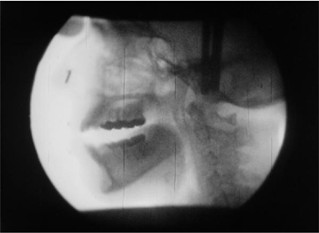

X-Ray, Ana Mendieta

16-mm-Film, transferiert auf HD Video, schwarz/weiß, Ton

Der Mitte der 1970er Jahre entstandene Film X-rays zeigt Bewegtbildröntgenaufnahmen des Schädels der kubanischen Künstlerin Ana Mendieta. Ihr Kopf wird aus verschiedenen Blickwinkeln durchleuchtet, während sie die immer gleiche Folge von Vokalen und Konsonanten wiederholt. Dabei nutzt sie Fluoroskopie-Technik der Universität von Iowa, die sonst dazu eingesetzt wird, Sprachstörungen zu diagnostizieren. Mendietas lautliche Äußerungen erinnern an eine Zungenrede in Trance; sie selbst hat sich als „neolithische Schamanin“ bezeichnet. Mit X-rays erschafft die Künstlerin ein Selbstporträt, in dem sich ihr augenscheinlich sichtbares Selbst im Röntgenblick zu einem Ur-Wesen transzendiert.